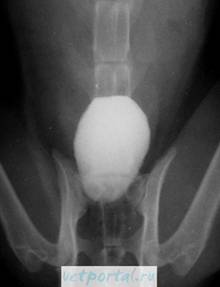

Кроме нисходящей цистограммы, получаемой при выполнении экскреторной урографии, иногда приходится прибегать и к восходящей (ретроградной) цистографии, для чего мочевой пузырь наполняют жидким рентгеноконтрастным веществом с помощью введенного в мочевой пузырь катетера. На ретроградной цистограмме более четко выявляется изображение опухоли мочевого пузыря, а также и внутрипузырно расположенная доброкачественная гиперплазия предстательной железы. На восходящей цистограмме при опухоли мочевого пузыря можно определить дефект наполнения. Однако при опухоли незначительных размеров контрастное вещество может прикрывать ее, и тога опухоль не видна. Иногда этот метод исследования позволяет выявить пузырно-мочеточниковый рефлюкс, возникающий вследствие нарушения замыкательного аппарата устья мочеточника из-за инфильтрации стенки мочевого пузыря или сдавления устьев аденоматозными узлами при сочетании опухоли мочевого пузыря с доброкачественной гиперплазией предстательной железы.

Мышечно-инвазивный рак мочевого пузыря (нормальная слизистая - желтая стрелка, опухоль - синяя стрелка)